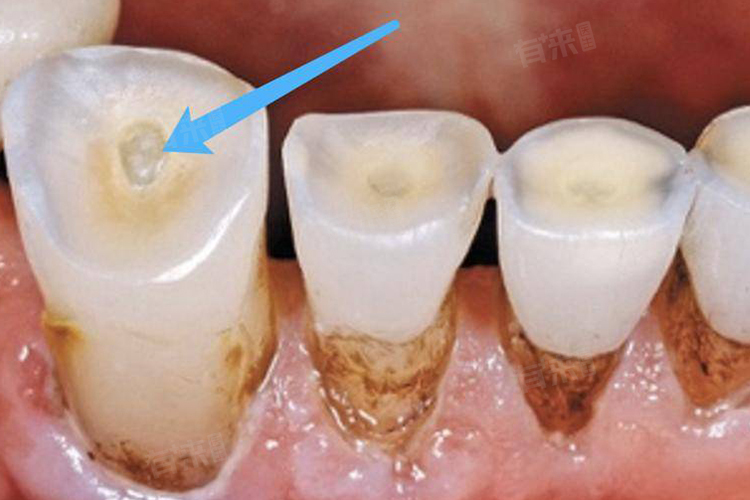

牙本质暴露是口腔科常见问题,多因刷牙方式不当、牙齿磨损、牙龈退缩等导致。牙本质内含有丰富神经末梢,暴露后外界刺激易传至牙髓,引发敏感疼痛。修复目的是阻断刺激传导,缓解症状,保护牙髓,如脱敏治疗、树脂充填修复等。

- 口腔视诊:医生直接观察口腔,查看牙齿表面有无磨损、楔状缺损、牙龈退缩等情况。磨损严重的牙齿,牙本质可能暴露;楔状缺损多位于牙齿颈部,若较深也会使牙本质外露;牙龈退缩时,牙根表面的牙本质会暴露。通过视诊可初步判断牙本质暴露原因及部位。

- X线检查:可查看牙齿有无龋齿,因龋坏进展至牙本质层也会导致牙本质暴露;还能观察牙槽骨高度,判断牙龈退缩是否伴有牙槽骨吸收,评估牙周支持组织状况,对明确牙本质暴露病因及制定治疗方案有重要意义。